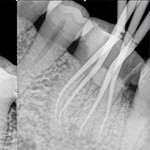

牙齿根管治疗就是我们俗称的堵牙,通过治疗,保留患牙。具体就是对牙齿,牙髓,根尖病变的一个治疗过程,通过清楚根管内的坏死物质,适当的消毒,填充牙齿根管,防止根尖周病变的一种治疗方法。

效果展示

根管治疗 根管治疗 根管治疗 根管治疗